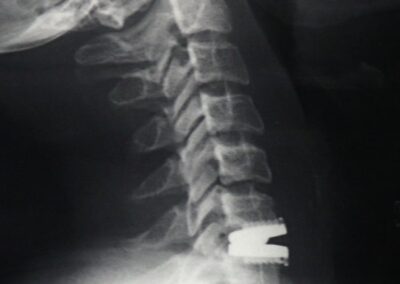

Cuando se trata de aliviar la presión sobre un nervio y el dolor de cuello, la cirugía usualmente incluye una extracción completa del disco o discectomía, seguido por el implante de un dispositivo espaciador o una prótesis total de disco. Esta cirugía se hace en la parte anterior del cuello (se le llama microdiscectomía y artrodesis o prótesis discal anterior). Afortunadamente, estos procedimientos muchas veces pueden realizarse usando técnicas de invasión mínima. La cirugía de invasión mínima no requiere incisiones grandes, sino que hace pequeños cortes y usa instrumentos y dispositivos minúsculos especializados durante la operación, como un microscopio y un endoscopio.